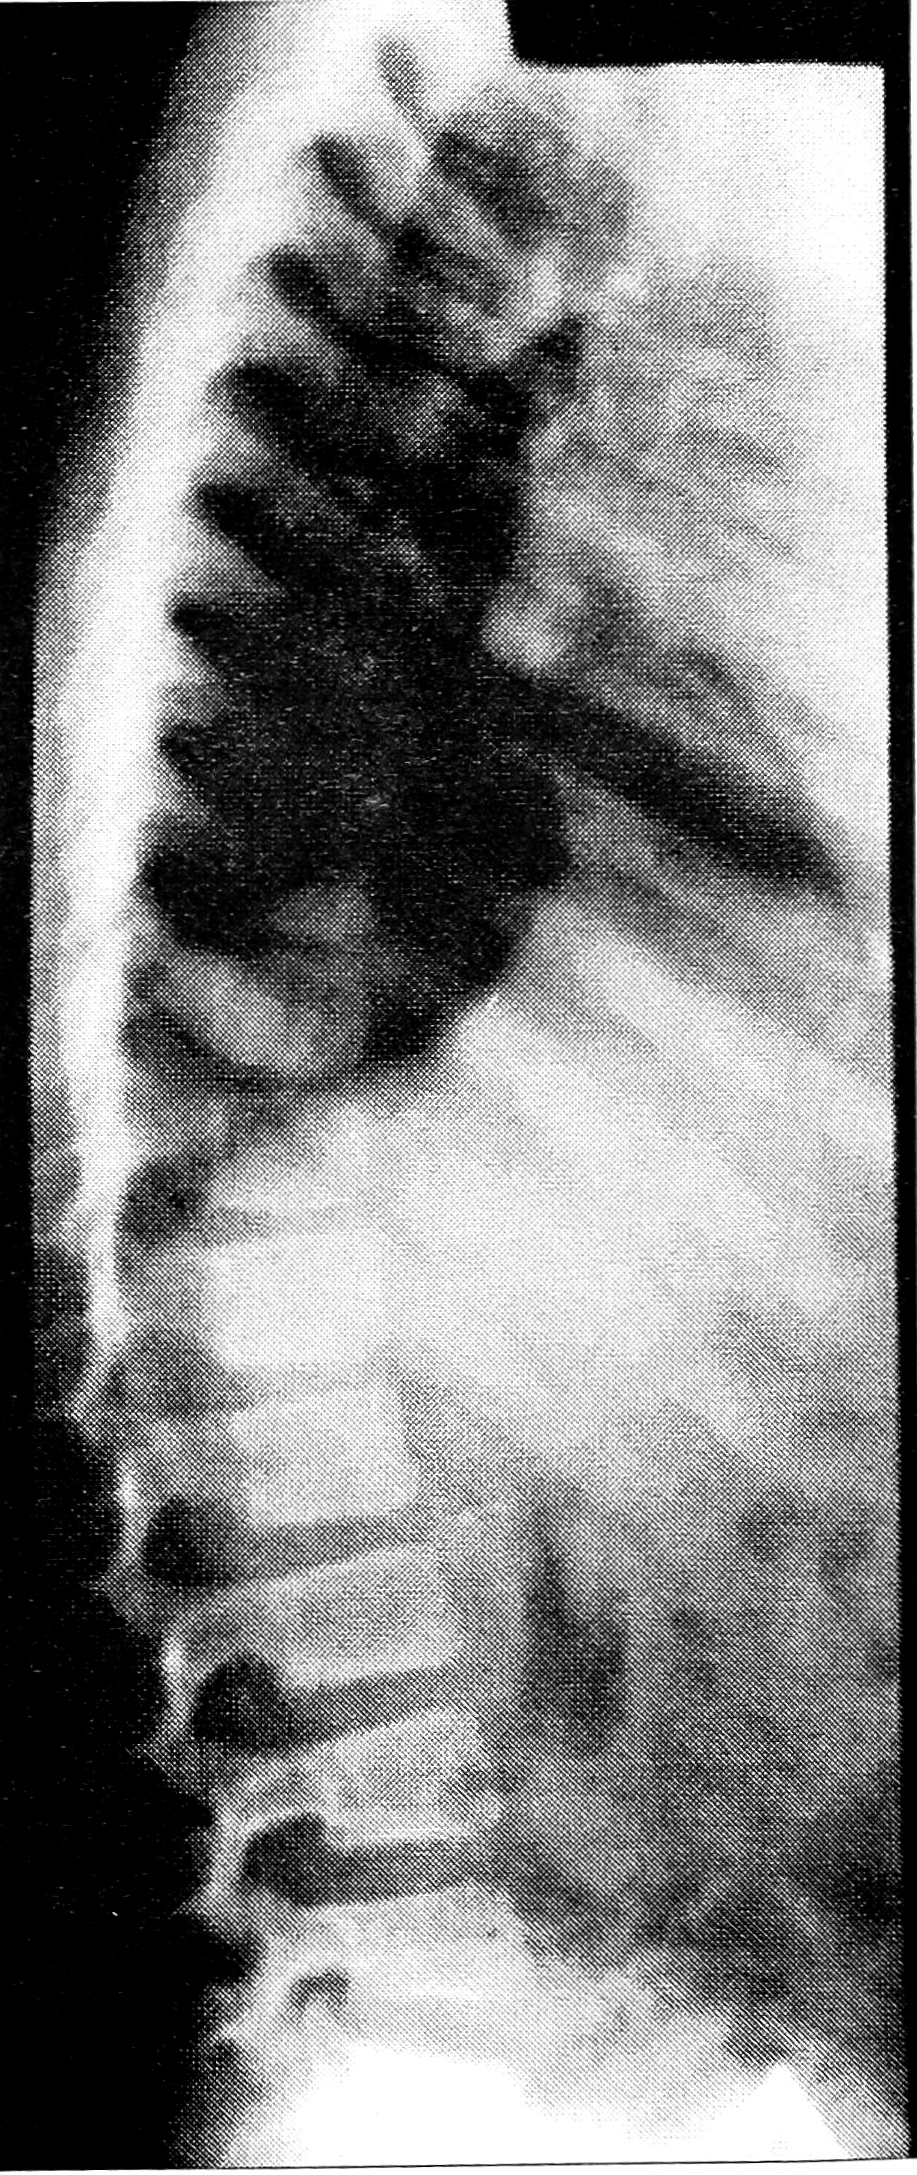

Рис. 4. Больной М. 5 лет. Клинический диагноз: односторонняя болезнь Пертеса.

В грудном отделе позвоночника высота дисков снижена, контуры тел позвонков неровные, шероховатые.

У 32 больных была произведена рентгенография грудного отдела позвоночника. У 22 из них выявлены умеренное снижение высоты межпозвонковых дисков и неровность (шероховатость) контуров замыкательных пластинок тел позвонков (рис. 4 на вклейке). Аналогичные изменения характерны для некоторых форм наследственных костных дисплазий.